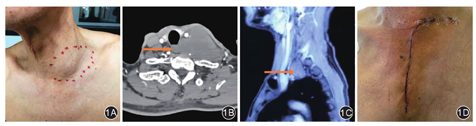

典型病例见图1。

回顾性研究。纳入符合要求的颈胸交界处肿瘤患者21例,其中男12例、女9例,年龄13.0~76.0岁(平均39.8岁)。患者首发病程3~90 d,平均16 d。21例患者中,颈肩部疼痛6例,锁骨上窝可触及肿物4例,胸闷症状明显3例,持续咳嗽3例,声音嘶哑2例,上肢水肿2例,患侧上肢麻木2例,出现上腔静脉综合征1例。

患者术前均行胸部增强CT扫描及三维重建,检查结果提示:颈胸交界处占位性病变。怀疑恶性肿瘤患者行腹部超声、头颅CT扫描及放射性核素骨扫描,或者行PET-CT检查,排除恶性肿瘤的转移可能。11例患者术前行穿刺病理检查:神经来源6例,甲状腺组织来源3例,淋巴组织来源2例。

全身麻醉。患者取平卧位,上胸部垫高,头向肿瘤对侧偏斜30°~45°。从锁骨远端的上缘开始,平行于锁骨做一横向切口,绕过胸锁关节到达胸骨上切迹,然后继续沿胸骨正中向下切至第3肋间水平。游离皮下组织后,自胸骨上切迹开始自上而下劈开胸骨上段至第3肋间水平,然后横向锯开胸骨至肋间隙,用小号胸骨撑开器撑开胸骨。仔细分离肿瘤组织,分别游离出无名动静脉、锁骨下动脉、上腔静脉等重要血管。其中2例患者发现肿瘤侵犯的左侧无名静脉管壁超过了周径的一半,行无名静脉置换;1例因肿瘤侵犯胸导管,行胸导管结扎;1例患者因肿瘤侵犯上腔静脉,转为全胸骨劈开同期行上腔静脉人工血管置换;4例因术前发现患侧上肺占位性病变,先切除颈胸交界处肿瘤,再应用胸腔镜辅助行患侧上肺叶切除术。患者完成肿瘤切除后,用胸骨钢丝或蝶形钢板固定胸骨上段,逐层关闭切口,经胸腔或者颈部放置引流管。